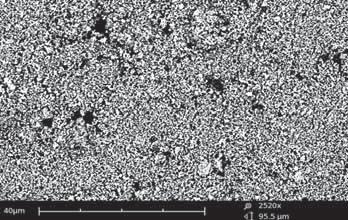

In the present study, an innovative, recently formulated material was tested. Vertise Flow is a flowable resin with adhesive properties, not requiring any additional adhesive step. According to the manufacturer the bonding mechanism is primarily based on the chemical bond between the phosphate functional group of GPDM monomer and calcium ions of the tooth. A micromechanical bond resulting from an interpenetrating network between Vertise Flow polymerized monomers and dentin collagen fibers also contributes to adhesion (Vertise Flow Product Manual, November 2009).